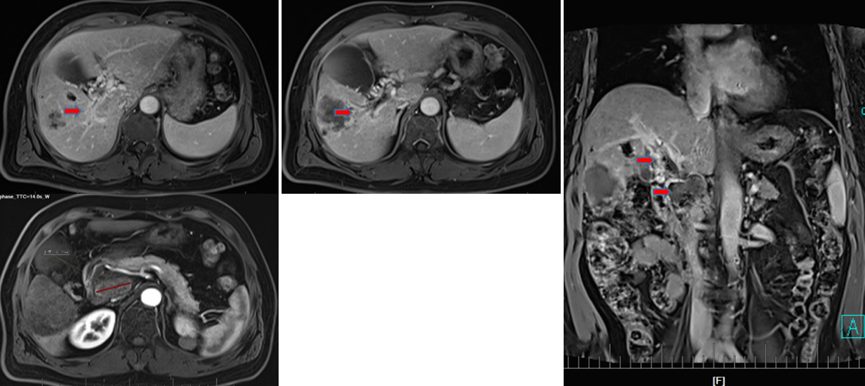

2022年3月9日复查MRI,可见门脉后方肿大淋巴结、腹膜后肿大淋巴无活性且已接近消失,肝右叶肿瘤无明显活性,门脉右支癌栓消退再通(图8);总体评价为完全缓解(CR)。

图片

图8.2022年3月9日复查MRI